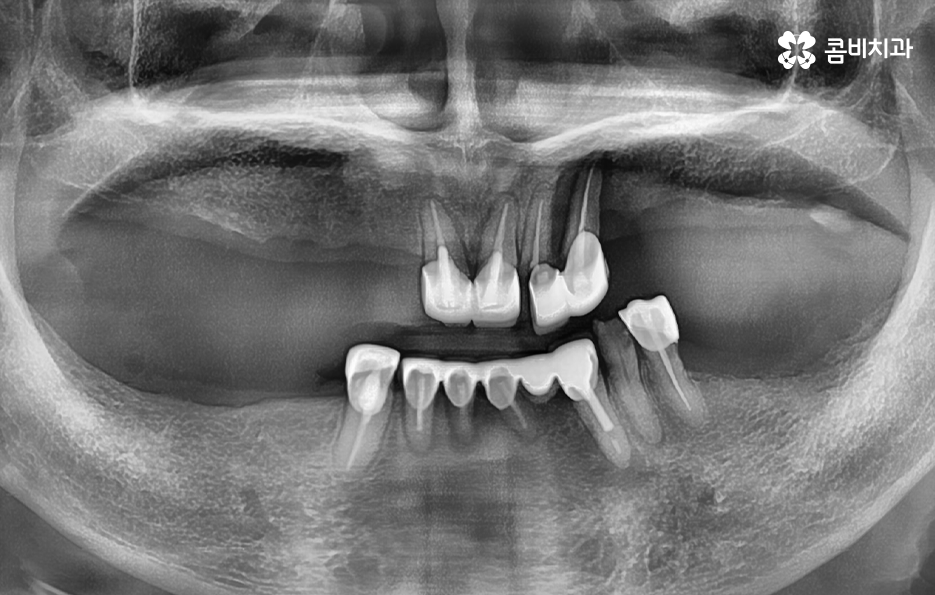

실제 치료 사례를 살펴보더라도 젊은 환자분들의 경우 원데이임플란트로도 치료가 가능한 사례가 많다면 노인분들의 경우 잇몸이 약해진 상태에서 치주염으로 치아를 잃게 된 경우가 많다보니 뼈이식을 추가적으로 받아야 하는 경우가 많이 있어요

5,60대 이후 환자 분들의 경우에는 잇몸 상태가 이미 좋지 않은 분들이 많고 전신질환이 있는 분들도 많기 때문에 임플란트 나이에 있어서는 보다 섬세한 치료가 필요한 경우가 좀더 많다고 볼 수 있어요

정리하면 임플란트 나이 단순히 나이만으로 치료 계획에 대해 쉽게 판단하기는 어렵겠지만 통계적으로 볼 때 치아의 주된 상실 원인과 임플란트의 원리에서 잇몸 뼈의 중요성을 따져볼 때는 젊은 환자분들에 비해 60대 이후 환자분들이라면 뼈이식을 추가로 받아야 한다거나 회복력과 전신질환에 대해서도 충분히 좀더 감안하여 치료 계획을 디테일하게 세울 필요가 있다는 것을 알 수 있는데요